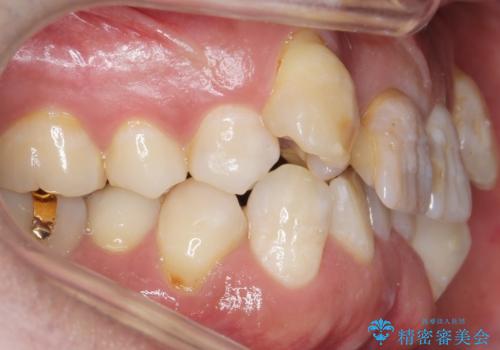

歯並びにより、そのままだときれいに被せ物をいれられない状態でした。

重度の叢生(歯並びのがたがた)のため、

患者様の「できるだけ短期間で治療を終わらせたい、セラミックが入れられたら良いので大がかりなことはしたくない」とのご要望により、3Dシミュレーションを何度も行い患者様とのコンサルを重ね、上顎左右犬歯と左下2を抜歯して②のプランである補綴前矯正(インビザライン)を行うことにしました。

寿命が長く機能的に重要な役目を果たす犬歯を抜くリスクや、矯正治療の仕上がりに限界があることをご理解頂いた上で治療を行っております。

犬歯は歯根が長く寿命も長い歯で、咀嚼機能時も重要な役目を果たすため、基本的に矯正の便宜抜歯に選択する歯ではありません。(一般的には第一小臼歯もしくは第二小臼歯が選択されることが多いです)

本症例では、様々な抜歯パターンの3Dシミュレーションを行い患者様と相談を重ねリスクをご理解頂いた上で、患者様のご希望により例外的に犬歯の抜歯を行いました。

小臼歯の歯根長が長いことを治療前にレントゲンで確認し抜歯部位を決定しました。

側方運動時に大きな役割をもつ犬歯がないため、今後の定期健診で歯の状態を注意深く観察していく必要があります。